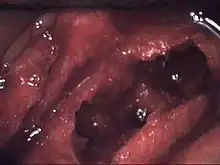

Osteonecrosis of the jaw of the upper left jaw in a patient diagnosed with chronic venous insufficiency